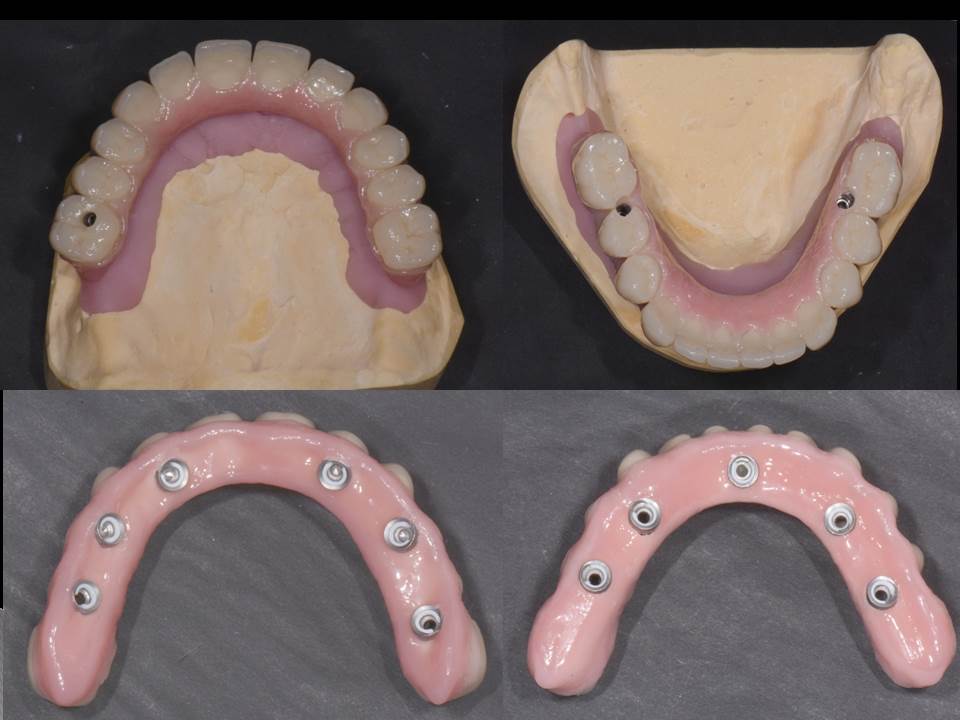

Prótesis fija OT BRIDGE

CASOS CLÍNICOS